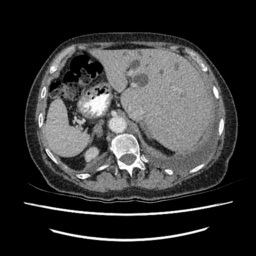

IV-E Results on the LiTS Challenge dataset.

We also implement ANT-GAN on the LiTS dataset and show some qualitative results in Figure 11. We observe that the lesions in the liver CT data appears with much lower contrast than in the brain MRI data. While our model can detect and modify the abnormal regions successfully, we note that there are more deformations than with the BratS18 dataset, which is a result of this more difficult task.

Refer to caption

Figure 11: Experimental results on the Liver CT data (LiTS).